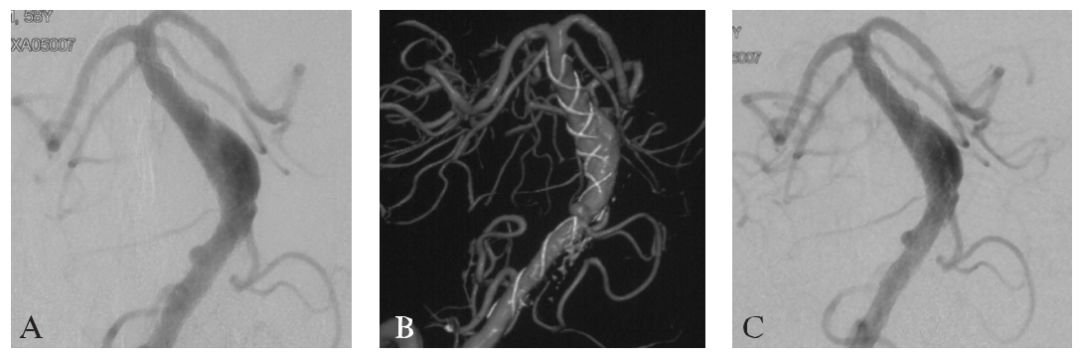

术后1个月复查CTA,提示病变管腔较前缩小(图16-2D)。术后5个月复查DSA提示原有的右侧支架外管腔消失,但病变左侧出现新的支架外管腔(图16-3A~C)。在球囊闭塞试验阴性的情况下,以Hypersoft 2mm/6cm、1.5mm/4cm弹簧圈在左侧椎动脉V4段的小脑前下动脉(AICA)开口与双侧椎动脉汇合部之间进行了椎动脉闭塞术(图16-3D)。

图16-3首次术后5个月时右侧椎动脉DSA随访及第2次介入治疗

A:右侧椎动脉造影显示支架外的右侧管腔消失(前后位观);

B:Dyna CT显示支架左侧新出现了血管的管腔膨出(箭头,前后位观);

C:Dyna CT显示支架外血管膨出的管腔(轴位);

D:以弹簧圈闭塞左侧椎动脉术后即刻造影表现(不减影前后位观)